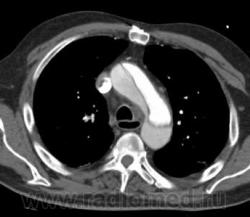

Рассоение аорты тип "A". Восходящий, нисходящий отдел, дуга, переход на брахиоцефалы...

Согласна. Только насчет брахиоцефала возражаю. Его не видно. То, что на 2 срезе, может оказаться верхней точкой дуги аорты. Нужны еще реконструкции, фронтальные например или весь объем.

Ага, я видно поторопилась. Когда я писала, были только аксиалы и то не все. Теперь, когда появились фронтальные реконструкции вижу переход на устье плечеголовного ствола. Есть признаки разрыва: жидкость в плевральной полости и немного в легком.

Ну, в данном случае понятно, что просвет который законтрастирован слабее - является ложным. Но в некоторых случаях, довольно сложно определить истинный и ложный просвет. В этом могут помочь: 1. Истинный просвет обычно меньше на аксиалах 2. СимПтом 'клюва' или 'beak sign" - наиболее характерный признак для ложного прросвета ( четко представлен в данном случае)то есть есть клювообразные выпячивания по периферии ложного просета в сторону истинного. 3. Cobweb sign - тоже характерен для ложного просвета ( мелкие 'ниточки' от отслоенной интимы в сторону ложного просвета. Другие признаки менее специфичны Доольно сложно иногда бывает отличить где исинный а где ложный просвет прихронических аневризмах.